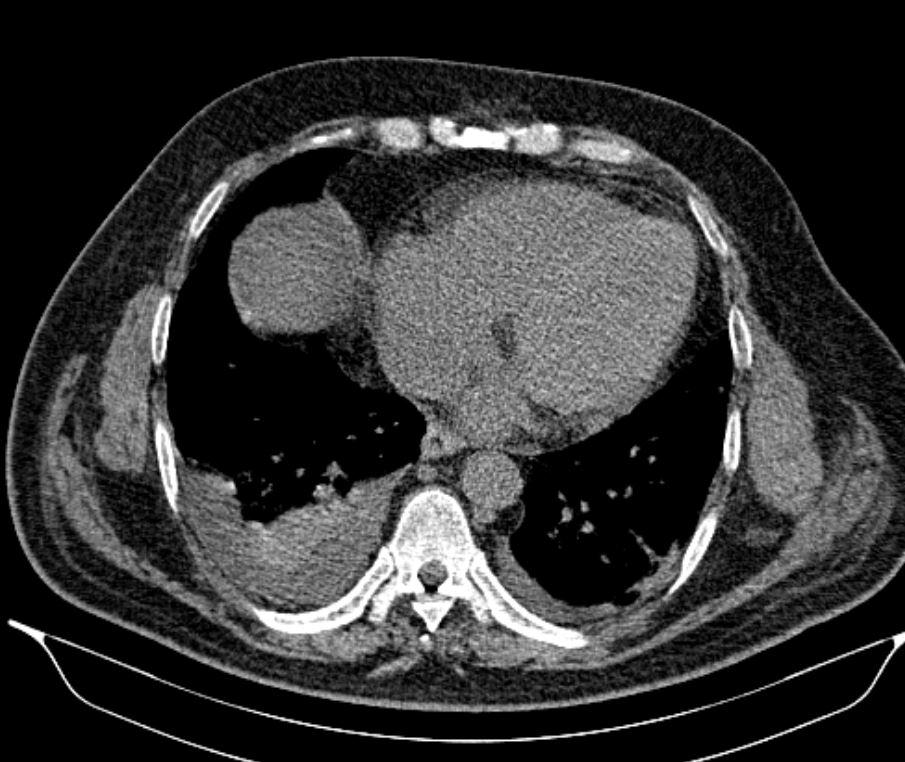

Case of the Week 24 2017 *50-year-old male with shortness of breath. What is the most likely diagnosis? Answer Answer: Pleural effusion and passive atelectasis Kategori:Cases Önceki yazı Case of the Week 27 2017 Sonraki yazı Case of the Week 25 2017